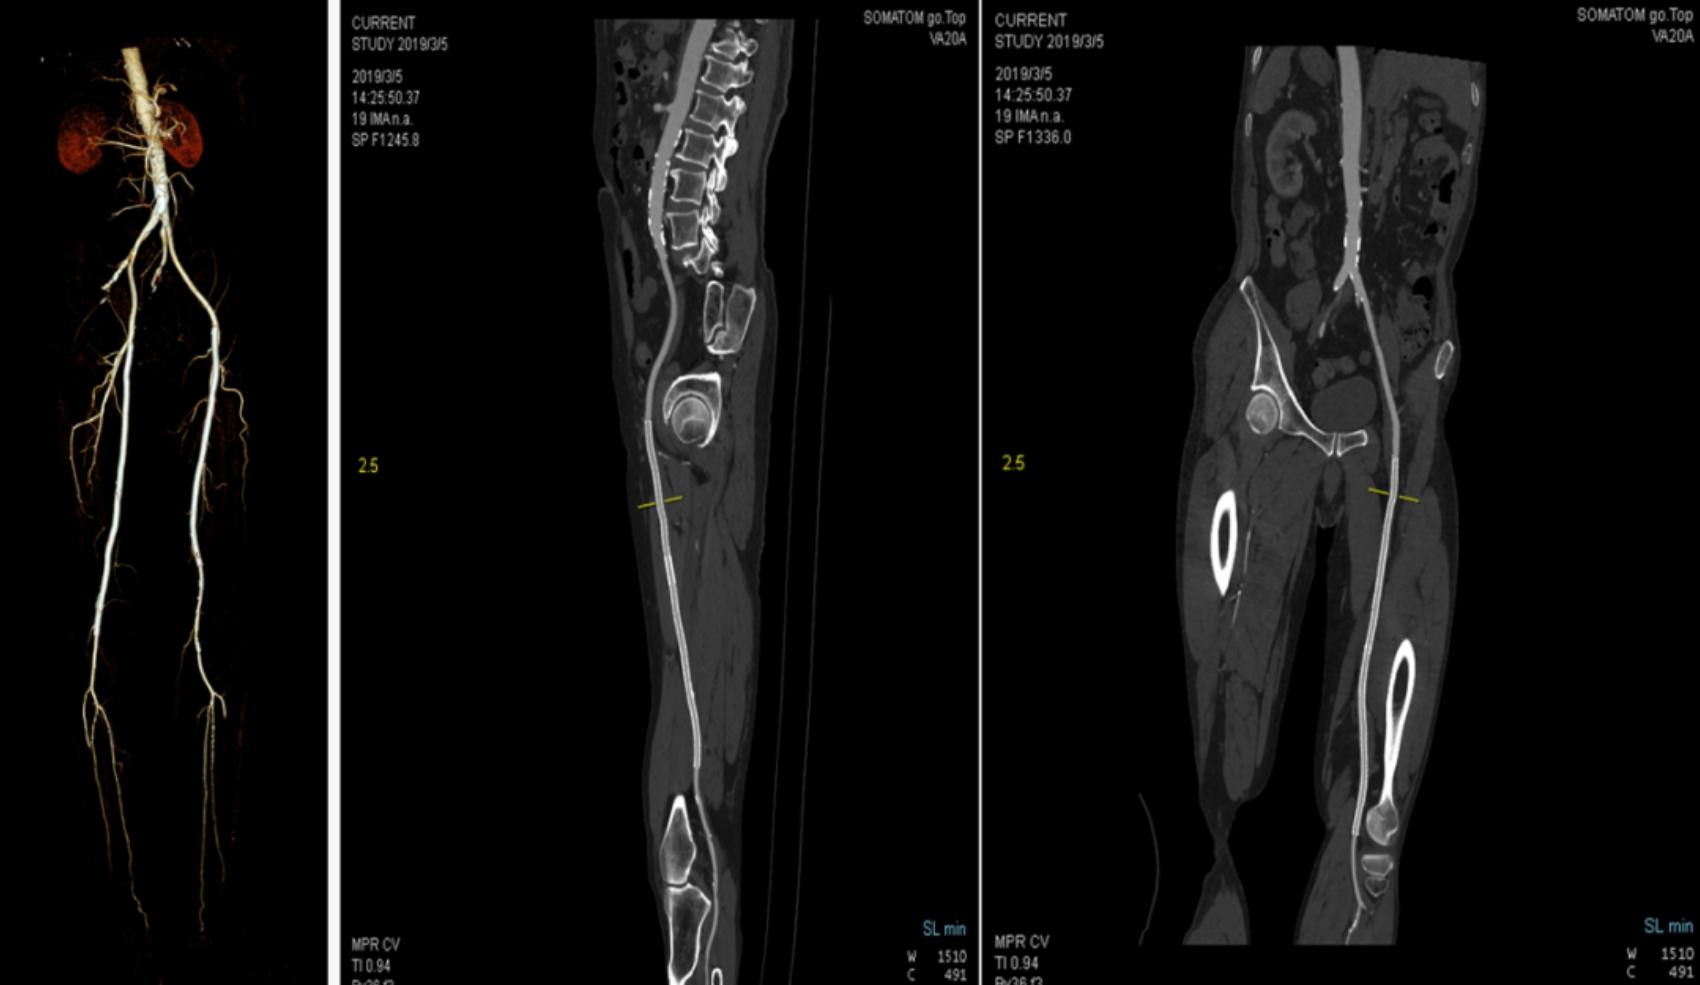

本次引進(jìn)的全新64排128層人工智能螺旋CT具有檢查更加精細(xì)、圖像更加清晰、掃描速度快和輻射劑量小等多種優(yōu)點(diǎn)。除了可進(jìn)行常規(guī)CT檢查、普通增強(qiáng)CT檢查外,還可對(duì)全身大血管、腦血管、心臟血管進(jìn)行檢查;強(qiáng)大的三維重建功能可發(fā)現(xiàn)普通DR、常規(guī)CT所難確診的病變。

該設(shè)備擁有單圈0.33秒/360°的極速掃描,超越之前所有多排螺旋CT,尤其適合心血管成像。胸部成像只需要3秒,全身成像9秒就可完成。

該設(shè)備,可以在短時(shí)間完成對(duì)冠狀動(dòng)脈缺血、肺栓塞、主動(dòng)脈瘤的一站式檢查,也可在在短時(shí)間完成對(duì)頭部血管、頸部血管、腦實(shí)質(zhì)血液灌注的一站式檢查,為腦卒中和急性胸痛患者的早期診斷和治療能力贏得黃金時(shí)間。